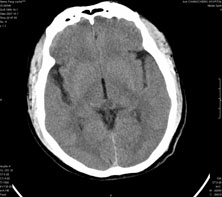

男,41岁,间断抽搐1小时,失神5分钟,bp130/90mmhg。低密度区ct值约16hu。

脑实质见多发散在的钙化点,左顶叶见一囊变灶,多考虑脑囊虫。

脑囊虫,部分囊内见头节。

脑实质见多发散在的钙化点,右颞、顶叶见囊性灶,考虑脑囊虫。

多发的囊泡(多发囊型)+多发的钙化(慢性钙化型)=混合型

多发脑囊虫—混合型!活动期